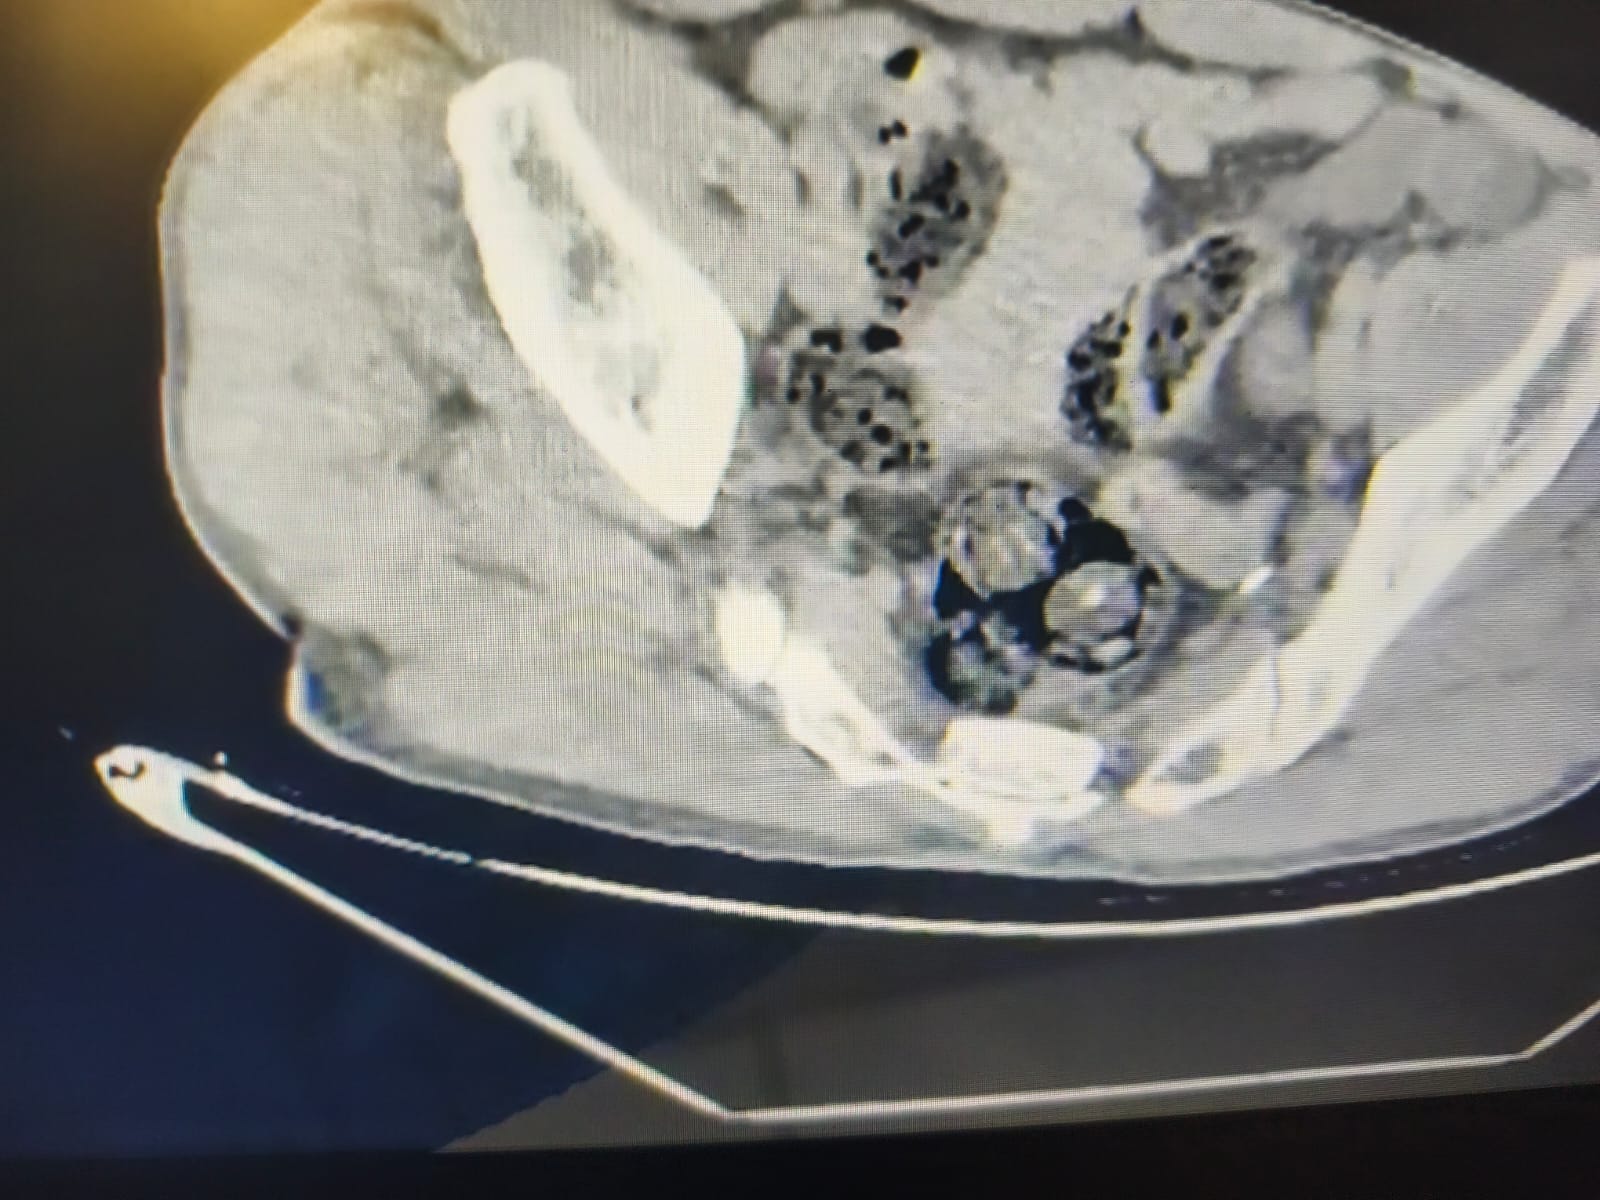

Şüphelinin üzerinde yapılan arama ve ardından radyolojik görüntüleme kullanılarak gerçekleştirilen iç beden muayenesinde şahsın makat bölgesinde 4 parça yabancı cisim olduğu tespit edildi.

Emniyet ve sağlık birimlerinin koordinasyonunda şahsın vücudundan çıkarılan yabancı cisimlerin, toplam 140 gram Metamfetamin olduğu belirlendi. Uyuşturucu maddeye derhal el konuldu.